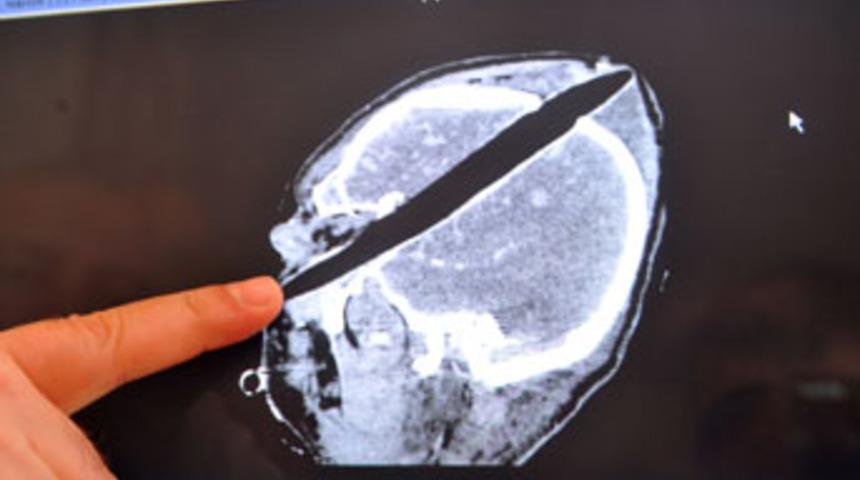

Hastanenin beyin cerrahi servisinde yapılan operasyonla Buyruk'un başına saplanan yaklaşık 30 santimetre uzunluğundaki tahta parçası çıkartıldı.

Beyin cerrahisi uzmanı Yrd. Doç. Dr. Erdoğan Ayan, yoğun bakım ünitesinde tedavisi süren Buyruk'un hayati tehlikesinin sürdüğünü bildirdi.